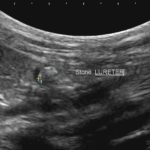

急性腎機能障害の猫ちゃんが(BUN>130mg/dl、Cre>14mg/dl、高カリウム血症)治療のため救急で対応しました。無麻酔CTでは両側に尿管結石が確認されました。著しく拡張している左腎の腎盂に一時的な腎瘻カテーテルを設置し、尿の排泄路の確保を行います。しかし、腎数値に改善は見られませんでした。腎盂造影を行うと拡張している腎臓において尿の産生と排泄は行われている様です。一方、腎盂拡張のほとんどない右腎の腎盂造影では尿の排泄が確認されません。今回の急性腎機能障害の原因は機能の残っていた右腎の急性尿管閉塞による急性腎障害と診断しました。左腎に関しては尿の産生はあるものの慢性腎機能障害であり、すでに尿濃縮能は失われていると判断しました。右腎の問題に対して尿管膀新吻合短尺型ステント設置術を行いました。術後は徐々に腎数値は低下し、腎機能の回復が得られました。一見すると腎盂拡張の顕著な側が急性腎障害の責任病変と判断しがちですが、片腎が十分に機能していれば腎数値に影響はほとんどなく、どちらの腎臓を治療対象とするか?エコー、CTなどの画像診断、血液検査、一時的な腎瘻カテーテルの設置、腎盂造影など総合的な判断が必要です。また判断がつかず、左右同時に治療が必要な場合もあります。